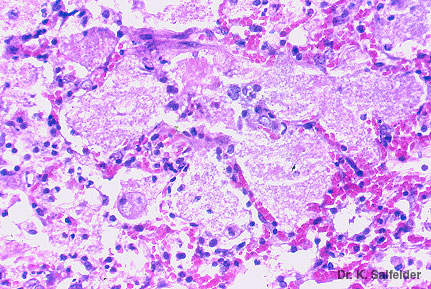

Abb. 1,38: Pneumozystose

Typisches Bild einer Lungeninfektion durch Pneumocystis carinii. In den Alveolen mit dem typischen schaumig-granulaeren Inhalt sind die Erreger bei dieser Faerbung nicht zu erkennen. HE-Faerbung